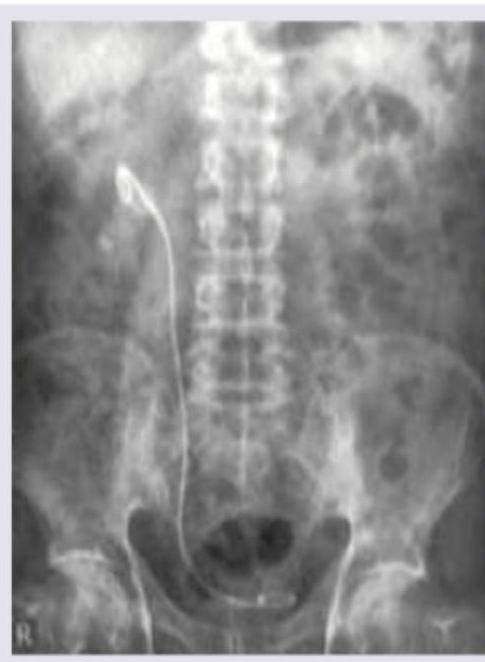

Which is incorrect about the procedure shown in the patient with right flank pain?

Explanation: In the provided image, there is a large, irregularly shaped, radio-opaque density in the right renal area, consistent with a **staghorn calculus**, likely causing the right flank pain. This type of calculus typically fills the renal pelvis and calyces. The question asks what is *incorrect* about the procedure shown, referring to **Extracorporeal Shockwave Lithotripsy (ESWL)**, a common treatment for kidney stones. ***Correct: No anesthesia is required*** - This statement is **incorrect** and is the correct answer to this negation question - ESWL typically requires some form of **analgesia or sedation** (e.g., intravenous fentanyl, midazolam, or even general anesthesia in selected cases) - The shockwaves cause significant discomfort as they are delivered, making **pain management essential** for patient comfort and compliance - While some patients with high pain tolerance may undergo the procedure with minimal analgesia, most require sedation *Incorrect: Contraindicated in hard stones* - This statement is partially correct, making it NOT the best answer - While hard stones (e.g., **calcium oxalate monohydrate, cystine, brushite**) are **more resistant** to ESWL with lower stone-free rates, ESWL is **not absolutely contraindicated** - ESWL can still be attempted for hard stones, though it may require multiple sessions, higher energy settings, or may ultimately fail, necessitating alternative treatments like **ureteroscopy** or **percutaneous nephrolithotomy (PCNL)** - True contraindications include pregnancy, uncorrected bleeding disorders, obstruction distal to the stone, and severe skeletal deformities *Incorrect: Done as outpatient procedure* - This statement is **correct** about ESWL, so it is NOT the answer to this negation question - ESWL is routinely performed on an **outpatient basis**, with patients typically going home the same day - Patients are monitored for a short period post-procedure (usually 1-2 hours) to ensure there are no immediate complications like significant hematuria or pain before discharge - Rarely, patients may require overnight observation if complications arise *Incorrect: Shockwaves pass through a water bath* - This statement is **outdated** but historically accurate - **First-generation ESWL machines** (1980s) utilized a **water bath** in which the patient was partially submerged to couple the shockwaves - **Modern lithotripters** (second and third generation) use a **gel pad** or **water cushion** placed directly on the skin, eliminating the need for water immersion while maintaining acoustic coupling - While technically incorrect for modern ESWL, the statement was historically true, making "no anesthesia required" a more definitively incorrect statement